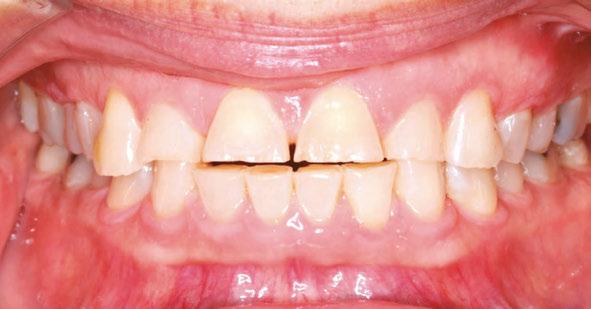

A 49-year-old female presented for an initial orthodontic exam with the chief complaint of bruxing and excessive wear on her teeth, especially the anterior. She was aware of the loss of tooth height and discussed restoration plans with her dentist. She had no history of previous orthodontic treatment and was wearing a maxillary flat-plane occlusal guard from her dentist. She was aware of daytime clenching and grinding but did not report any TMJ pain, clicking, or popping. Maximum opening and range of motion were within normal limits. Cephalometric

Figures 1-5: Initial dental photos

analysis showed that she had a brachycephalic skeletal pattern, but ANB and inter-incisal angles were normal. Occlusal wear in and of itself does not affect patient quality of life,3 but some patients are self-conscious about the appearance of their short, worn teeth, which is the category that this patient fits into. Her chief concern was to improve her dental esthetics.